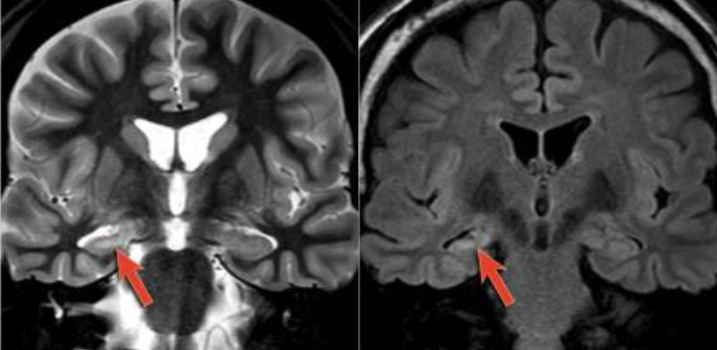

Esclerose mesial temporal

Observe a perda de volume, que indica atrofia e causa aumento secundário do corno temporal do ventrículo lateral.

O sinal alto no hipocampo reflete a gliose.